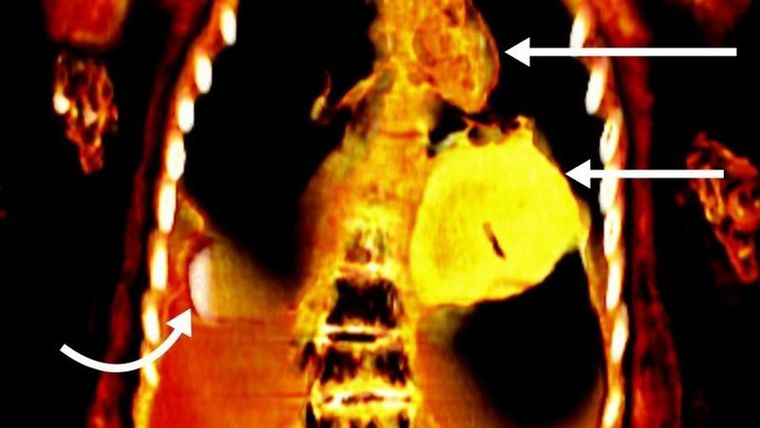

No obstante, esto cambió cuando un equipo liderado por la doctora Sahar Saleem, de la Universidad de El Cairo, decidió revisar la momia, utilizando para ello un tomógrafo computarizado.

Las imágenes obtenidas revelaron que el cuerpo del fallecido portaba 49 amuletos de 21 tipos diferentes, muchos de ellos elaborados de oro y, por ello, se le ha bautizado a la momia como el "chico de oro", anunció Saleem en un artículo publicado en la revista Frontiers in Medicine.

Los escáneres permitieron determinar que el joven era de clase alta, pues "tenía dientes y huesos sanos, sin evidencia de mala nutrición o enfermedad" y porque sus restos fueron objeto de un proceso de momificación "de alta calidad, que incluía la extirpación del cerebro y de las vísceras".

Un equipo de investigadores egipcios utilizó un tomógrafo para examinar una momia de hace 2300 años y que tenía más de un siglo almacenada en los depósitos del Museo de El Cairo.

Las imágenes mostraron que debajo de las mortajas que cubrían el cuerpo del joven había un objeto de dos dedos de longitud junto al pene no circuncidado del fallecido, una lengua de oro dentro de la boca y un escarabajo con forma de corazón también hecho del precioso material que estaba debajo de la cavidad torácica.

Las imágenes también mostraron que el cuerpo del joven estaba ataviado con sandalias y guirnaldas de helechos.

"La tomografía computarizada representa un avance significativo en radiología. En lugar de usar una sola imagen, se pueden combinar cientos de proyecciones de secciones delgadas (rebanadas) del cuerpo para crear un modelo tridimensional completo", concluyó.